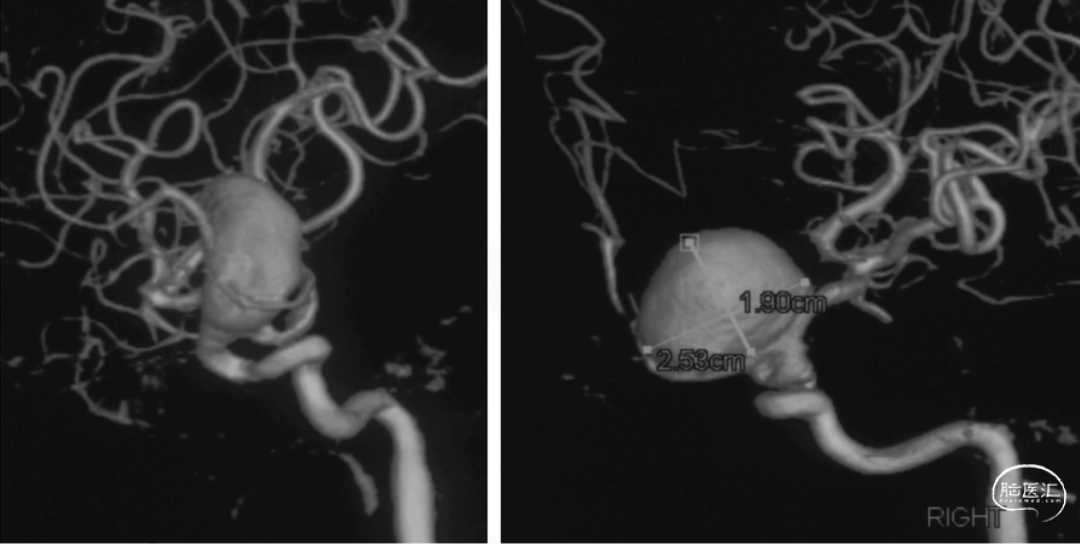

载瘤动脉近端直径4.24mm,远端直径3.05mm,选择通桥麒麟™血流导向密网支架 TQL-40-45。

微导丝囊内成绊,超选到大脑中动脉M1远端。

撤出微导丝,送入弹簧圈微导管至瘤腔内。

固定输送系统,回撤微导管,逐步释放通桥麒麟™血流导向密网支架头端,至头端张开为V型。

继续送入弹簧圈填塞。

再次造影确认打开情况,用微导丝继续按摩支架尾端。